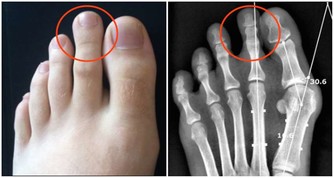

膽經在下肢的巡行路線是沿股、下肢外側中線下行至小趾、次趾之間。

有個很容易找到的標誌,就是沿著褲子中間的那條線至膝蓋側面,

主要是環跳、風市、中瀆、膝陽關四個穴位。